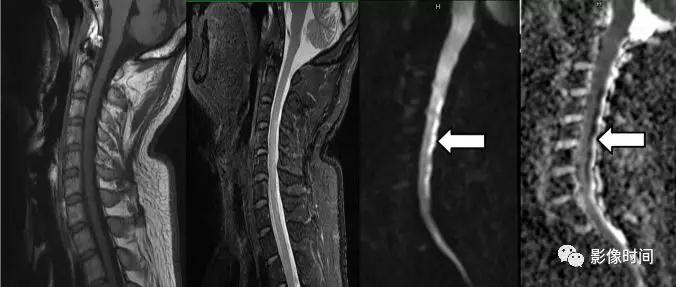

多发性硬化(Multiple sclerosis,MS)亦是一种严重的中枢神经系统自身免疫脱髓鞘病变,免疫球蛋白分泌 B 细胞和浆细胞的克隆性扩增,可使 CSF 中出现寡克隆带特征。

MRI:

脊髓:颈髓较常受累,病灶 T2WI 呈高信号,T1WI 呈稍低信号,轴位常分布于前索、侧索或者后索,长轴 ≤ 2 个连续阶段椎体,急性期呈斑片状、结节状或环形强化。

病灶位于侧索、长度小于3个椎体节段